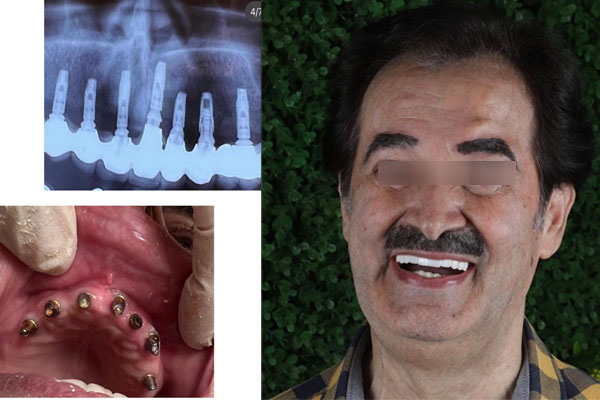

دندانپزشکی دکتر جباری و دکتر میر محمد صادقی

- خدمات ایمپلنت دندان:

- ایمپلنت (برترین برندهای روز دنیا)

- اتو کلاو کلاس B

- درمان ریشه (اندو) با استفاده از دستگاه روتاری هوشمند

- روکش های PFM و زیرکونیوم

- ترمیمی

- پروتزهای ثابت و متحرک

آدرس: جنت آباد جنوبی، میدان چهار باغ، ساختمان سبز، پلاک ۱۴۸، طبقه اول، واحد ۱۴

تلفن: 44620836